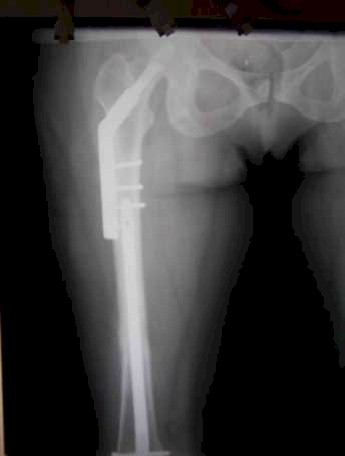

Caso 1. DHS en fractura intertrocantérica e intramedular retrogrado para fractura tercio medio del fémur.

Caso 1. DHS en fractura intertrocanterica e intramedular retrogrado para fractura tercio del fémur con signos de consolidación.